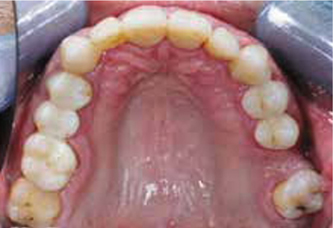

Afb. 3

Occlusaal aanzicht van de bovenkaak.

Bij het extraoraal onderzoek zie ik een lichte hypertrofie van de m. masseter. Intraoraal tref ik een ernstig versleten dentitie aan waarbij de slijtage niet passend bij de leeftijd kan worden genoemd (afbeelding 2-7 en tabel 1) .